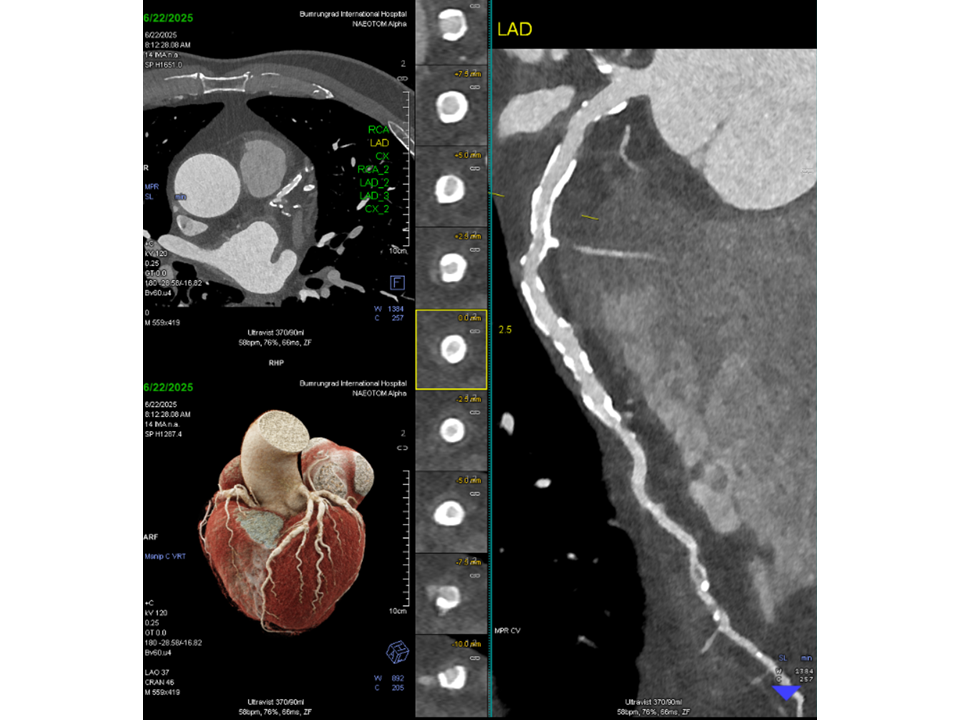

To overcome the diagnostic limitations typically associated with such extensive calcification, the patient was scanned using the Quantum Plus HD protocol on the NAEOTOM Alpha system. The ultra high-resolution PCD-CT acquisition with spectral data reconstruction6 enabled clear visualization of the coronary lumen and confident assessment of stenosis, despite the dense calcific burden. Invasive catheter angiography was avoided in this case.

- Reduction of Blooming Artifacts: Dense calcifications often obscure the coronary lumen in conventional CT. PCD-CT minimizes blooming by reducing the influence of high-attenuation calcium on surrounding tissues, allowing clearer visualization of vessel patency.

- Enhanced Spatial Resolution: Submillimeter resolution at 0.2 mm enables more precise delineation of coronary anatomy, even in densely calcified segments.

- Lower Partial Volume Averaging: Smaller voxel dimensions reduce averaging across tissues, which helps prevent overestimation of plaque size and improves accuracy in lumen assessment.

- Improved Contrast-to-Noise Ratio (CNR) with Monoenergetic Imaging: Spectral reconstruction at optimal keV levels enhances contrast between iodine and calcium while suppressing image noise, improving diagnostic confidence in complex cases.